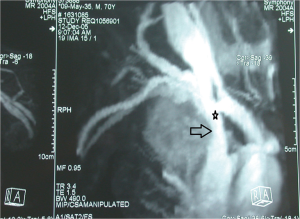

在涉及侵犯上腔静脉的NSCLC的术前管理中,可以通过从双上肢注射造影剂的腔静脉造影术研究浸润的范围,即使该技术可能因覆盖结构的存在而存在严重偏倚,这可能导致图像不确定[33,34]。最近,CT血管造影(CTA)和磁共振血管造影(MRA)被用于评估血管受累(图1)。与腔静脉造影相比,CTA和MRA在区分不同解剖结构和最终血管浸润程度方面显示出更高的灵敏度[33];有趣的是,一些作者报告非增强和增强MRA的相似灵敏度,这可能进一步降低检测的侵入性[35,36]。此外,Ohno及其同事[37]报告,使用心电图(electrocardiographically,ECG)触发MRA的放射图像质量更好。最后,必须进行超声心动图检查,以排除右心房血栓的存在[34]。